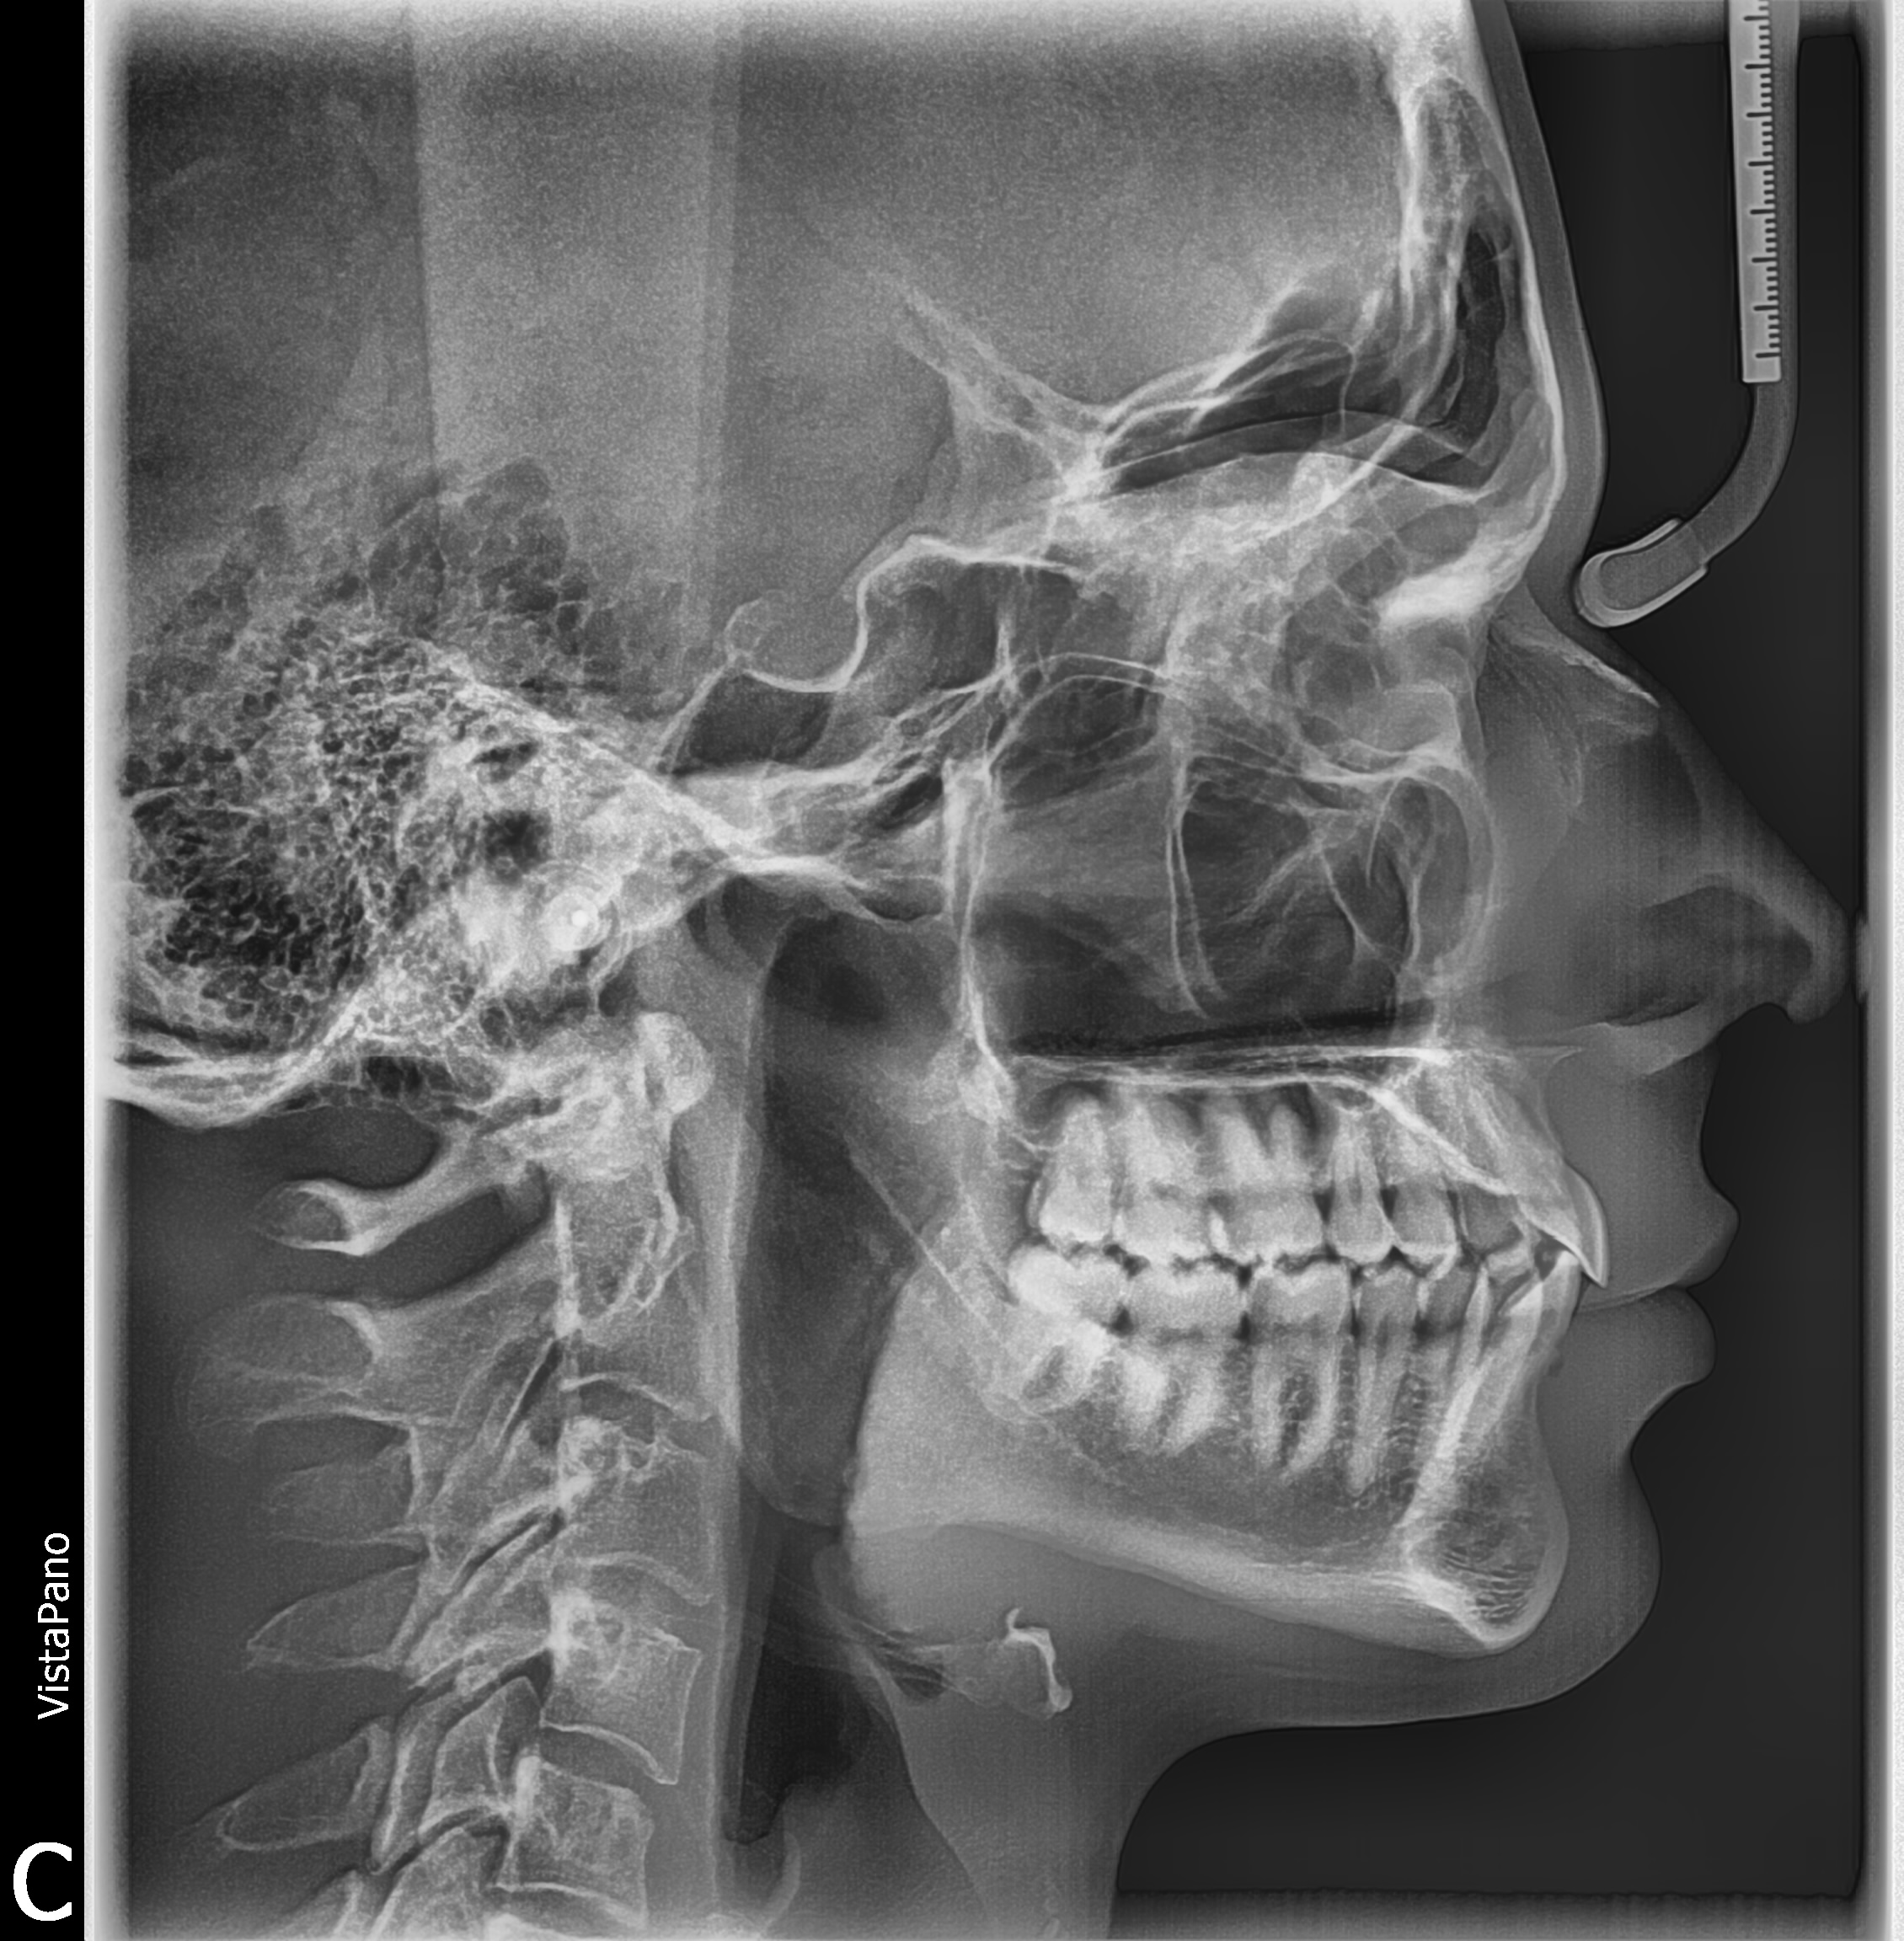

I just got approved for Damon braces and I’m scheduled to get them on in two weeks. I’m pretty happy as my mouth is my biggest failo.

I am slightly recessed due to an 80% deep bite. However I have a wide palate, so thankfully there is no need for maxillary expansion, just a dental arch widening.

I’m attaching a before photo for anyone interested in my before/after progress.

Your x ray looks like mine

I do have a recessed maxilla causing my mid face to look long. I am working on ways to fix this. Hopefully this is one of them.